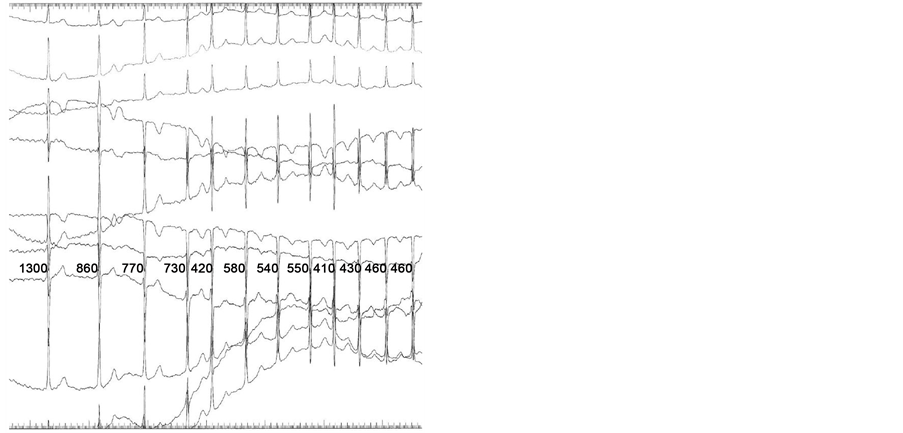

Due to her ECG, coupled with the chief complaint ofpalpitations, there was a concern for WPW syndrome. The patient was referred to the Pediatric Electrophysiology Lab for an adenosine challenge. Consent was obtained from the patient and her mother. A peripheral IV was started in the right antecubital fossa and she was placed on a continuous ECG monitor. Her baseline heart rhythm was normal sinus rhythm at a rate of 90 bpm. Adenosine 12 mg was administered by rapid IV push followed by a 10-milliliter saline flush. After a short delay, A-V node block was noted, with multiple non-conducted P-waves (Figure 1).

After 6.5 seconds, the patient went into atrial fibrillation, which persisted for 45 seconds, then self-terminated. The patient remained stable during this period with normal blood pressure and verbal response. Of note, the patient described her episode of atrial fibrillation as qualitatively different from her palpitations. In spite of inducing atrial fibrillation, the adenosine challenge was effective in ruling out accessory pathway atrioventricular conduction and WPW syndrome in this patient due to atrioventricular block.

Figure 1. (a) Normal sinus rhythm is demonstrated at baseline; (b) After adenosine is administered, there is atrioventricular block (star), followed by spontaneous onset of atrial fibrillation (arrow); (c) Atrial fibrillation; (d) Return to normal sinus rhythm is demonstrated following spontaneous cardioversion from atrial fibrillation.